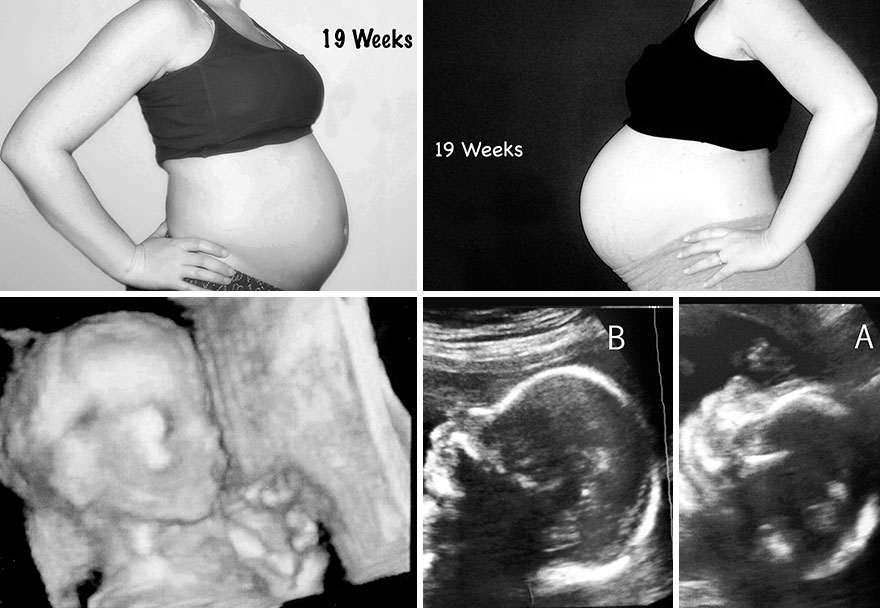

Αυτές οι φωτογραφίες δείχνουν τις διαφορές στο μέγεθος της κοιλιάς μου, στις δύο εγκυμοσύνες. Δείχνουν, επίσης, τους υπερήχους των αντίστοιχων εβδομάδων.

19η εβδομάδα κύησης